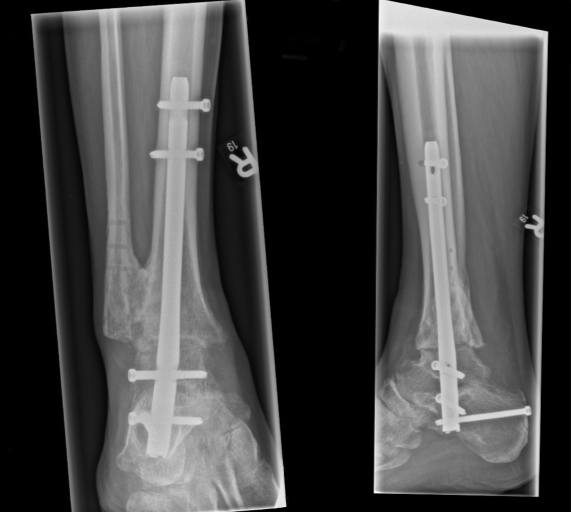

Abbildung 1 [Abb. 1]